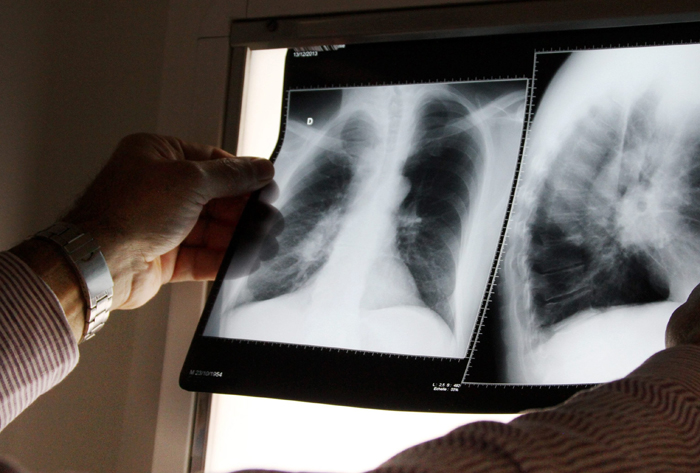

Le patient tousse (il peut y avoir un peu de sang dans les crachats). Il a de la fièvre, des sueurs nocturnes, il n'a plus d'appétit, maigrit, peut ressentir des douleurs à la poitrine. Il est très fatigué. Tous ces symptômes concernent la tuberculose pulmonaire.

La tuberculose peut avoir des conséquences graves si elle n'est pas prise en charge comme une compression des voies respiratoires, un épanchement de liquide dans la plèvre….

Le patient tousse (il peut y avoir un peu de sang dans les crachats). Il a de la fièvre, des sueurs nocturnes, il n'a plus d'appétit, maigrit, peut ressentir des douleurs à la poitrine. Il est très fatigué. Tous ces symptômes concernent la tuberculose pulmonaire.

La tuberculose peut avoir des conséquences graves si elle n'est pas prise en charge comme une compression des voies respiratoires, un épanchement de liquide dans la plèvre….